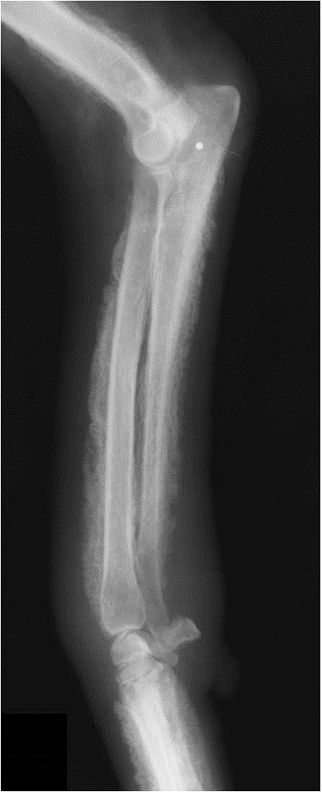

premature distal radius physis closure roentgen signs

gap - radius and humerus, radius and carpus

no real ALD

which physis closed early

radius